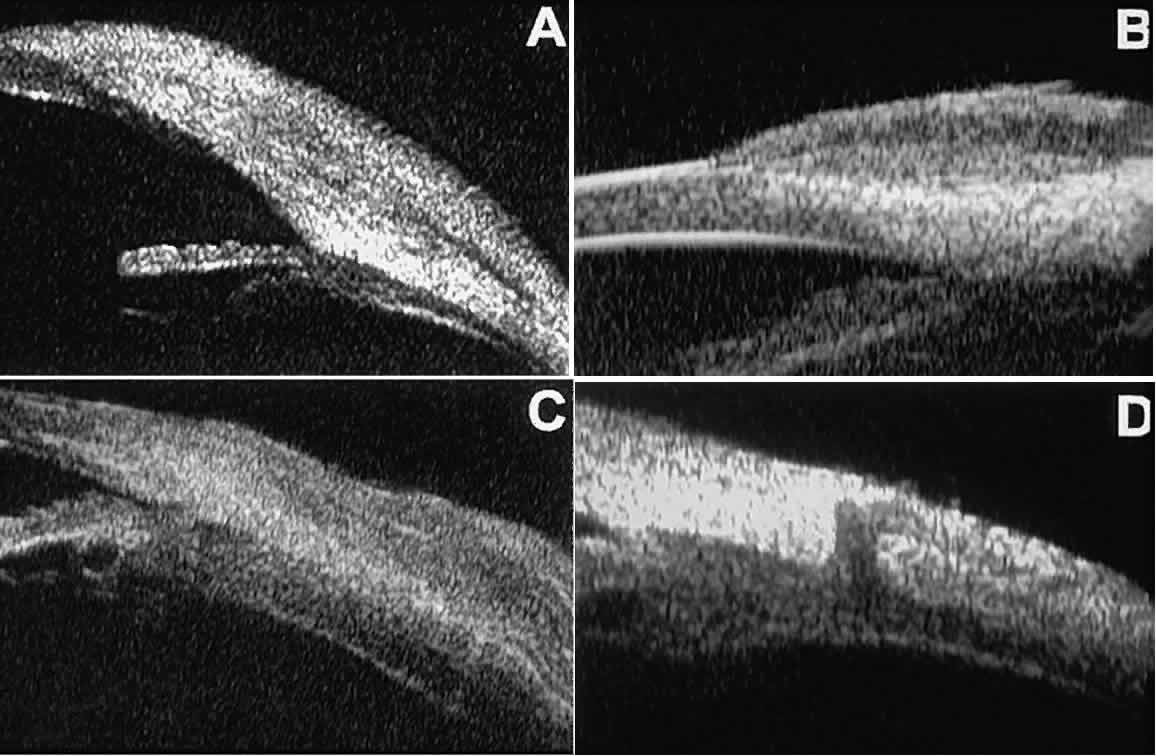

Postoperative UBM imaging of the anatomic changes caused by glaucoma surgery

often helps to explain mechanisms of success and failure of the

various surgical procedures (Fig. 12).3,4 After laser iridotomy, UBM can show whether the iridotomy is partial thickness (see Fig. 12A) or full thickness (see Fig. 12B) and whether the plane of curvature of the peripheral iris has changed

compared with the pretreatment findings. After trabeculectomy (see Fig. 12C), UBM can show whether the scleral aperture is patent or blocked internally, whether

the peripheral iridectomy is open or blocked, and whether

the filtering bleb is flat, shallow, or deep.9 After tube shunt surgery (see Fig. 12D), UBM can show the position of the tip of the tube and whether its orifice

is open or plugged.  Fig. 12. UBM features in glaucomatous eyes after treatment or filtering surgery. A. Incomplete peripheral iridectomy created by laser. B. Full-thickness peripheral iridectomy created by laser. C. Postoperative features of trabeculectomy including peripheral iridectomy, inner

filtering bleb. D. Tube shunt projecting radially into anterior chamber; note that the tube “shadows” deeper structures. Fig. 12. UBM features in glaucomatous eyes after treatment or filtering surgery. A. Incomplete peripheral iridectomy created by laser. B. Full-thickness peripheral iridectomy created by laser. C. Postoperative features of trabeculectomy including peripheral iridectomy, inner

scleral defect, thin residual scleral flap, and overlying conjunctival

filtering bleb. D. Tube shunt projecting radially into anterior chamber; note that the tube “shadows” deeper structures.